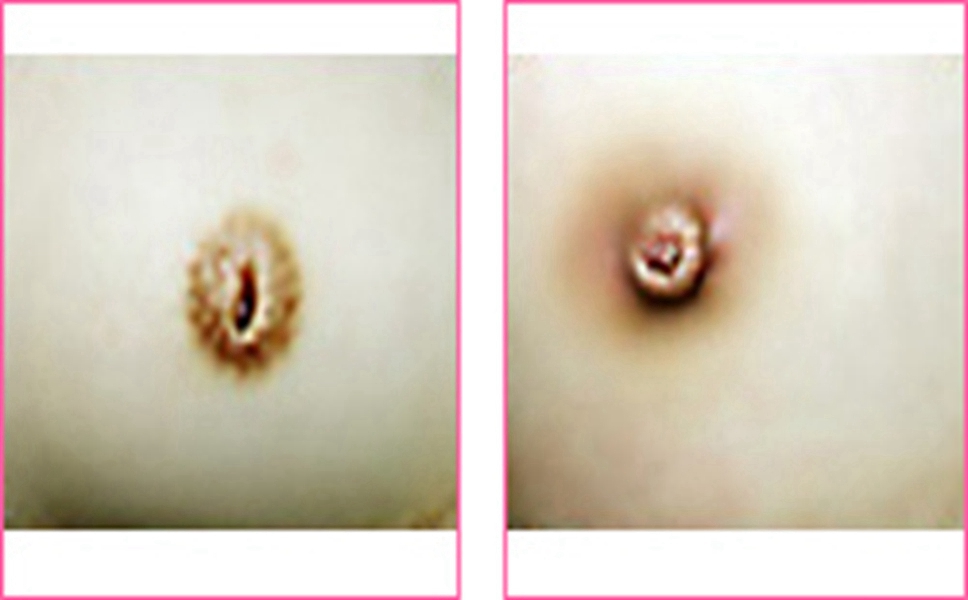

乳頭內陷圖片

乳頭內陷治療效果

乳頭內陷

中度乳頭內陷矯正

怎麼才算乳頭內陷

嚴重乳頭內陷

什麼叫乳頭內陷